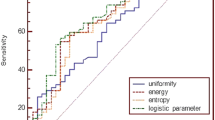

During a median follow-up of 36 months, tumor recurrence was found in 26 patients (22.6%). Multivariate analysis demonstrated that CE-T1 MPP and T2 kurtosis at SSF3–5, CE-T1 MPP at SSF6, and CE-T1 SD at unfiltered images were independent predictors of RFS (p < 0.05). Regarding the 2-year RFS for CE-T1 MPP and T2 kurtosis at SSF5, and CE-T1 MPP at SSF6, patients with > optimal cutoff values demonstrated significantly worse survival than those with ≤ optimal cutoff values (p < 0.05).